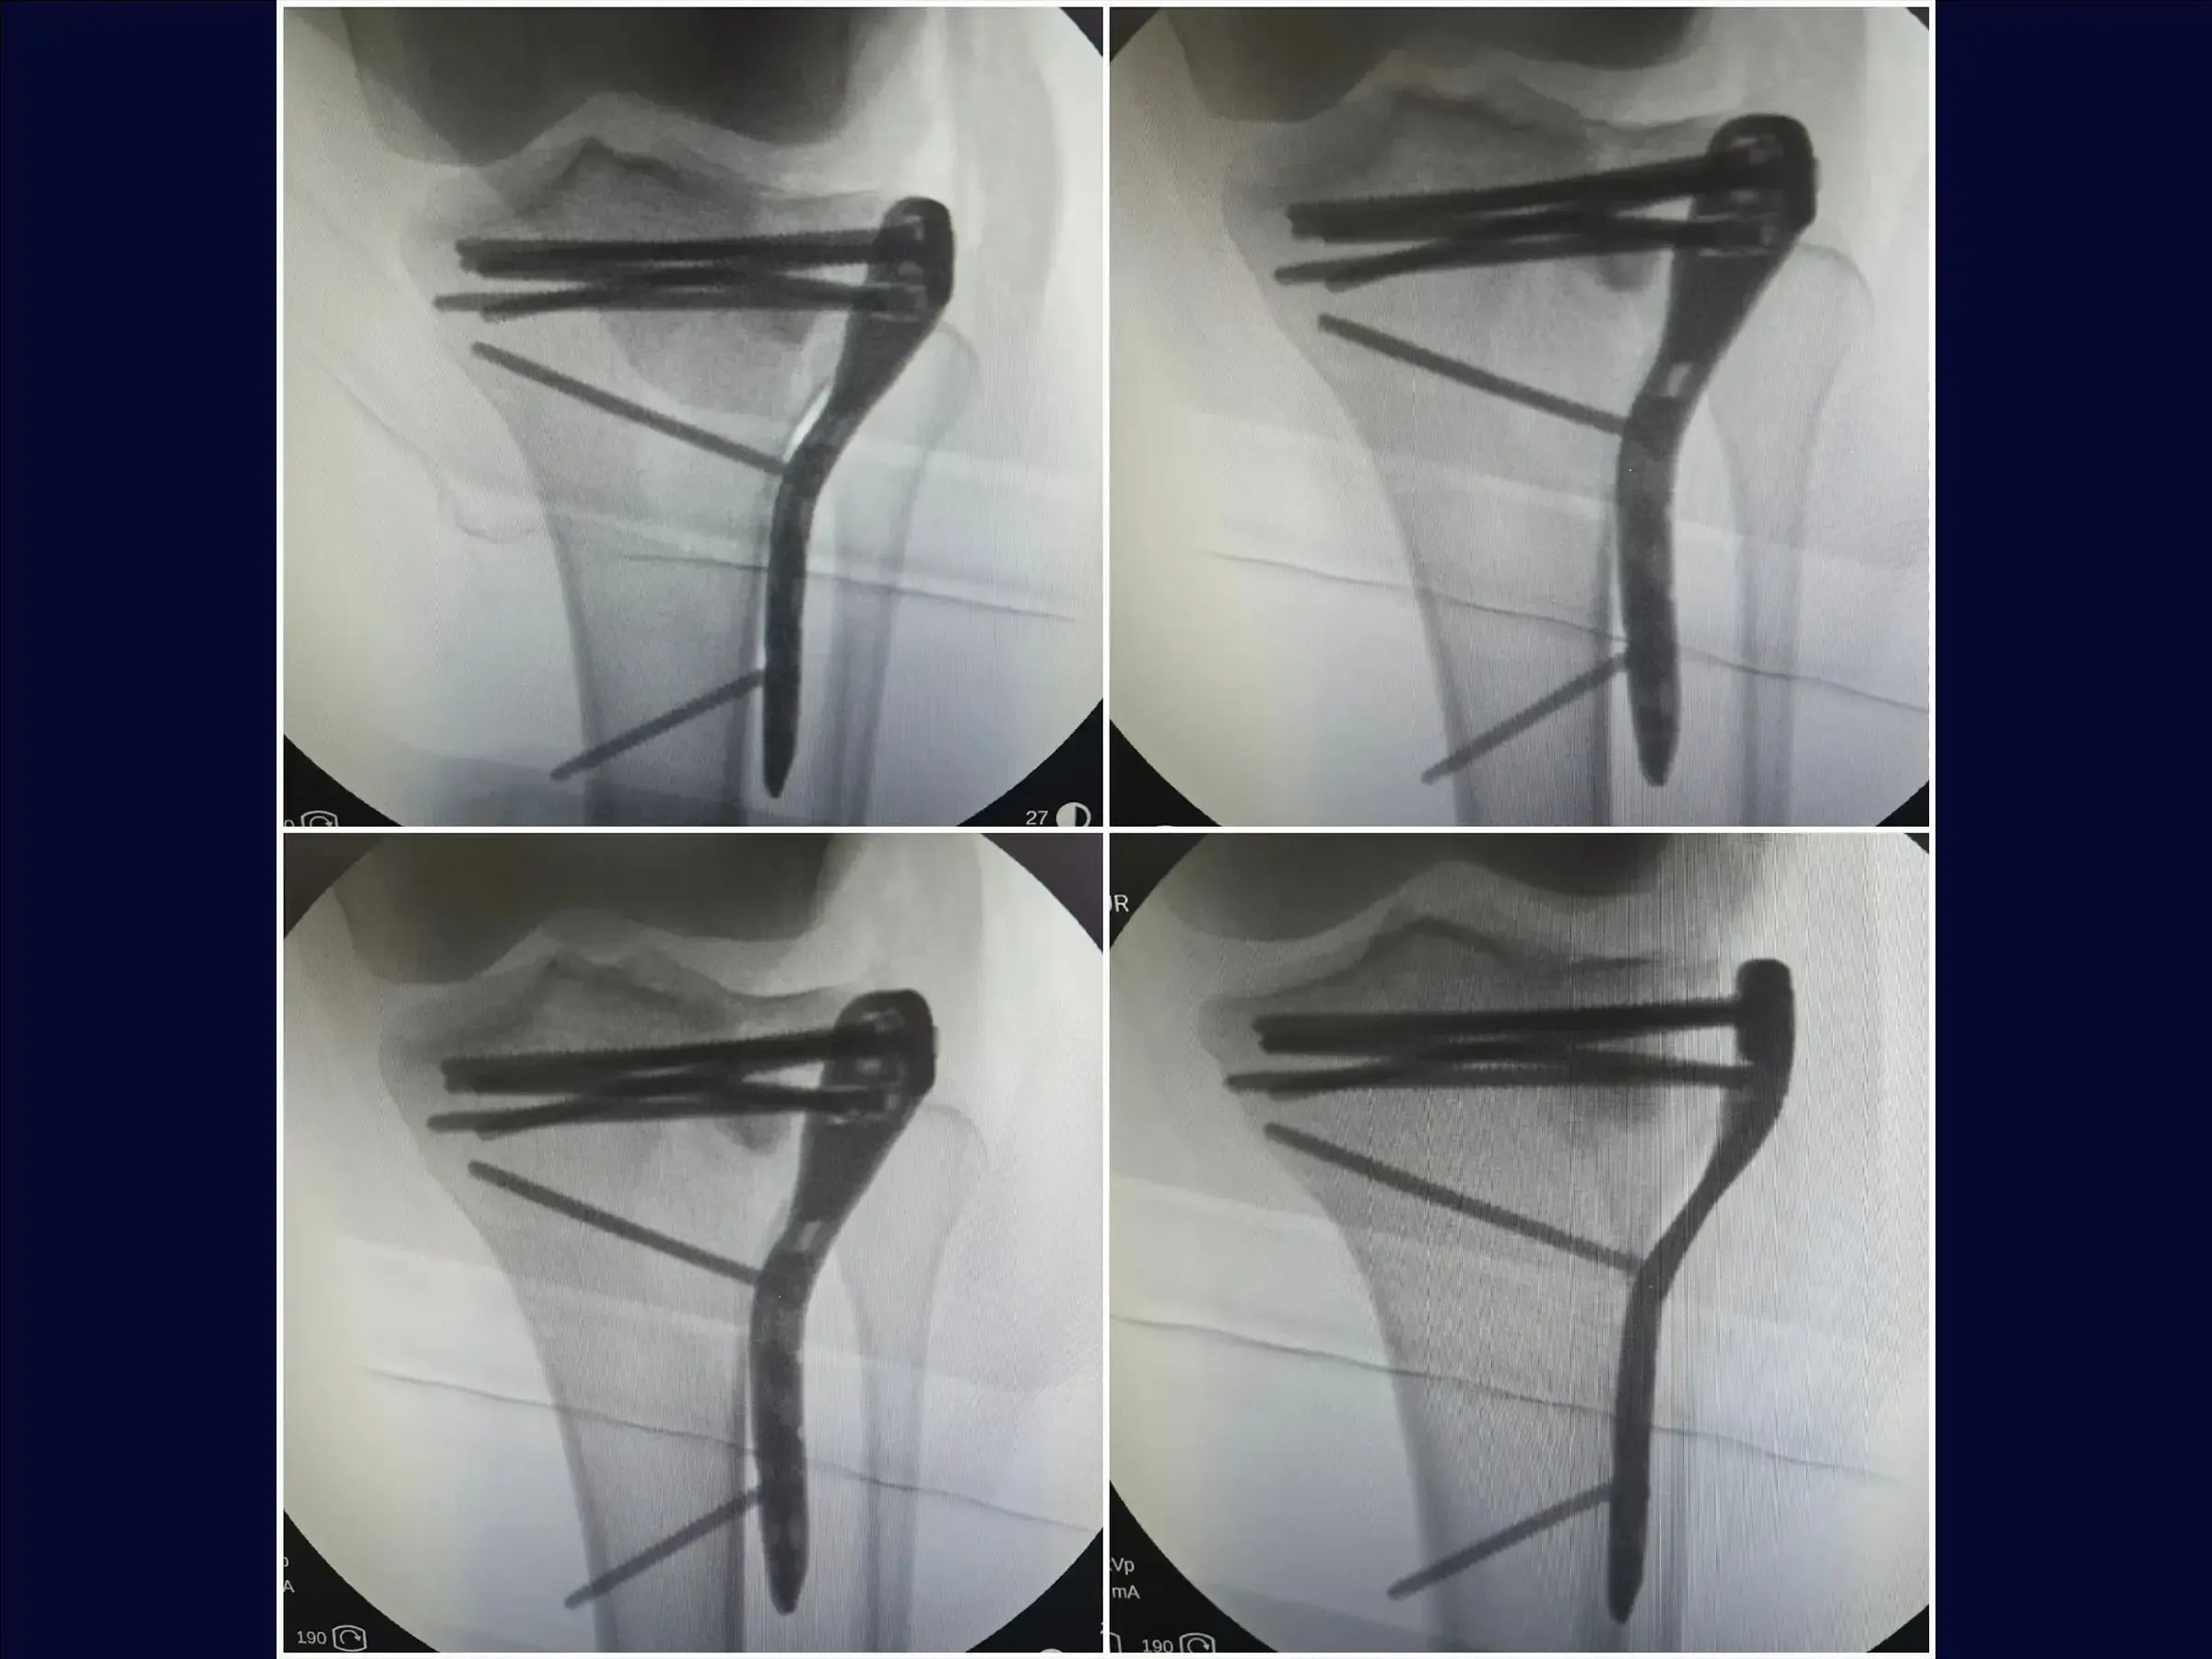

- Técnica de osteotomía incompleta (elástica) para levantar el fragmento hundido.

- Fijación con placa y tornillos para reducción y estabilización anatómica.

- Osteotomía Incompleta (Elástica): Aprendizaje de una técnica que preserva la corteza anterolateral inferior, permitiendo la elevación elástica del fragmento sin crear un segmento suelto, lo que simplifica la reducción y estabilización.

- Elevación precisa de la depresión: metodología para levantar el bloque óseo impactado de manera uniforme, con sobrecorrección discreta para la acomodación y estabilidad del injerto, utilizando control bimanual.

- Estrategia de Fijación Estable: Aplicación de la placa con tornillo en un punto estratégico para la compresión inicial, seguido de la inserción de tornillos bloqueados subcondrales , formando una red de soporte articular.